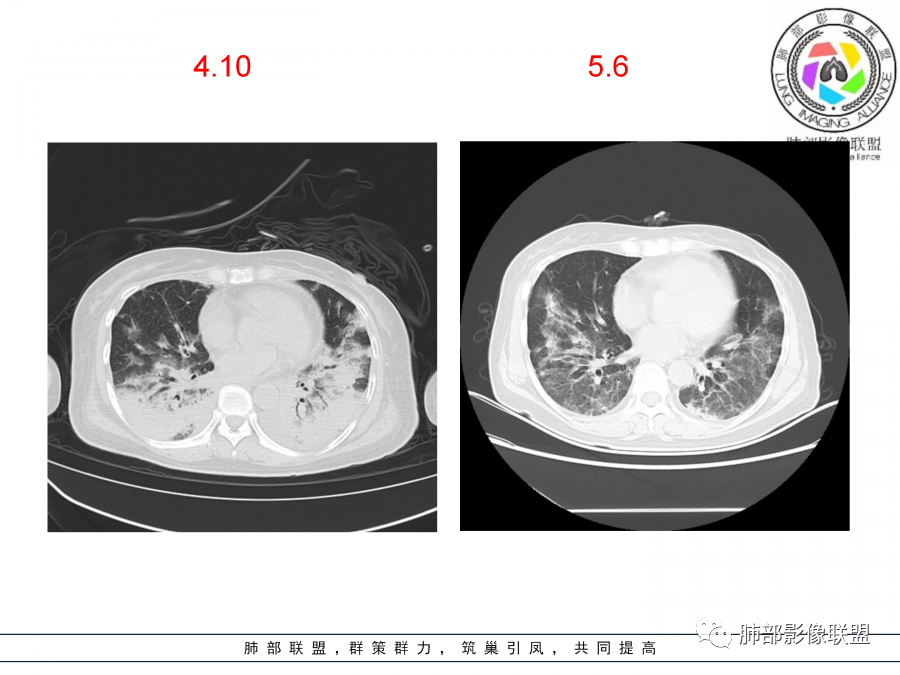

影像,第一次双肺中下叶胸膜下多发斑片状实变影,部分融合成,周围散发磨玻璃影,磨玻璃影内可见小叶间隔及小叶内间隔增厚,病变平行于胸膜,第二次间隔8天,双肺实变影明显进展,有重力作用,支气管近端堵塞,进展较快,临床有发热,血沉高,狼疮SLE阳性,考虑1:OP(机化性肺炎)2:SLE相关肺炎,建议支气管镜灌洗液病原学检测。

老年女性,咳嗽咳痰伴发热7天,白细胞不高,血沉快,降钙素原不高。其他化验未见明显异常,狼疮全套抗Ro/SSA阳性,双肺野靠近胸膜下磨玻璃实变影,支气管通畅,有充气征,沿胸膜下分布,有细网格征,7天后进展明显,实变影加重,胸膜肥厚,胸水不明显,心包少量积液?抗感染治疗无效,考虑非感染性疾病可能性大,结缔组织相关性肺病?狼疮性肺炎?机化性肺炎?鉴别病毒性肺炎。

老年女性,咳嗽咳痰发热7天。无气促。白细胞计数不高,PCT稍高,PPD(+),抗Ro/SSA阳性。CT:双肺野靠近胸膜下磨玻璃实变影,支气管通畅,有充气征,沿胸膜下分布,有细网格征。予抗生素治疗,8天后复查胸部CT见病灶范围扩大,实变影加重,胸膜肥厚,胸水不明显。抗感染治疗无效,考虑有:1.非感染性疾病:结缔组织相关性肺病,支持点:肺部CT表现为间质性炎症病变,抗RO/SSA(52)阳性;2.病毒性肺炎:患者无气促症状,可能性小;3.肺结核。

第一次双肺中下叶胸膜下多发斑片状磨玻璃及实变影,病变平行于胸膜,支气管通畅,8天后,双肺实变影明显进展范围扩大,部分支气管近端堵塞,进展较快,胸腔积液,抗感染治疗无效,考虑:非感染性疾病:结缔组织相关性肺病。鉴别机化性肺炎。